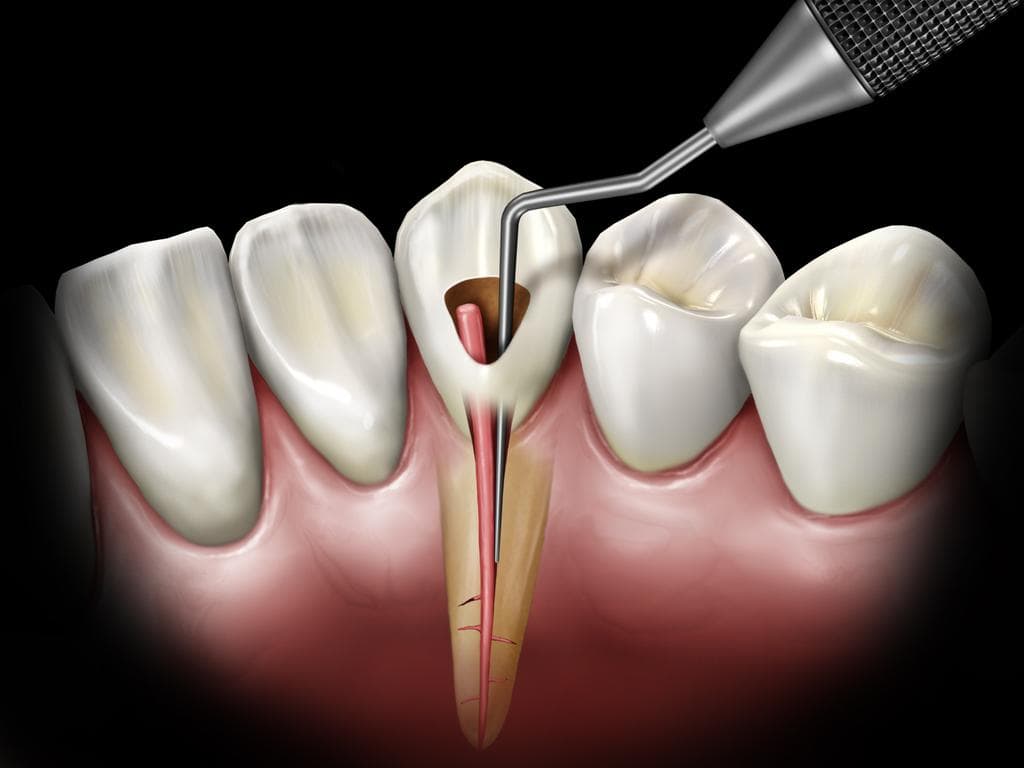

Modern ve çağdaş bir anlayışla sizlere daha iyi bir hizmet vermek en büyük görevimiz. Gülüşünüze gülüş katmak, sizlerle beraber mutlu olmak en büyük gayemizdir. Son teknolojik cihazlarla tam teşekküllü bir poliklinik hizmeti veriyoruz. Diş hekimiliği ve diş sağlığı hastalıklarının tüm branşlarında hizmet veriyoruz.